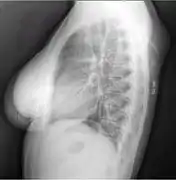

A physical exam is typically the easiest way to diagnose it. Rarely, a tissue biopsy or imaging may be required. The imaging modality of choice is magnetic resonance imaging (MRI) because it has superior sensitivity of distinguishing it from liposarcoma as well as mapping the surrounding anatomy.[22]

X-ray of a lipoma

X-ray showing lipoma